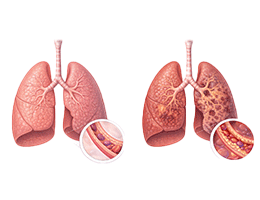

기관지염 (Bronchitis)

천식 (호흡기계 (기관지, 폐))

기관지확장증 (Bronchiectasis)

폐섬유증 (Pulmonary Fibrosis)

기관지천식 (Bronchial Asthma)

간질성폐질환 (Interstitial Lung Disease)

운동유발천식 (Exercise-induced Asthma)

특발성폐섬유증 (Idiopathic pulmonary fibrosis)